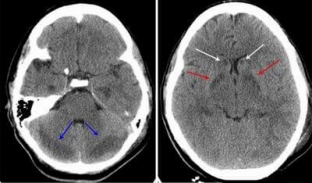

It is important to understand that it will not be possible to diagnose cerebral edema on your own, for this, specialists use the following methods:

- CT and MRI of the brain;